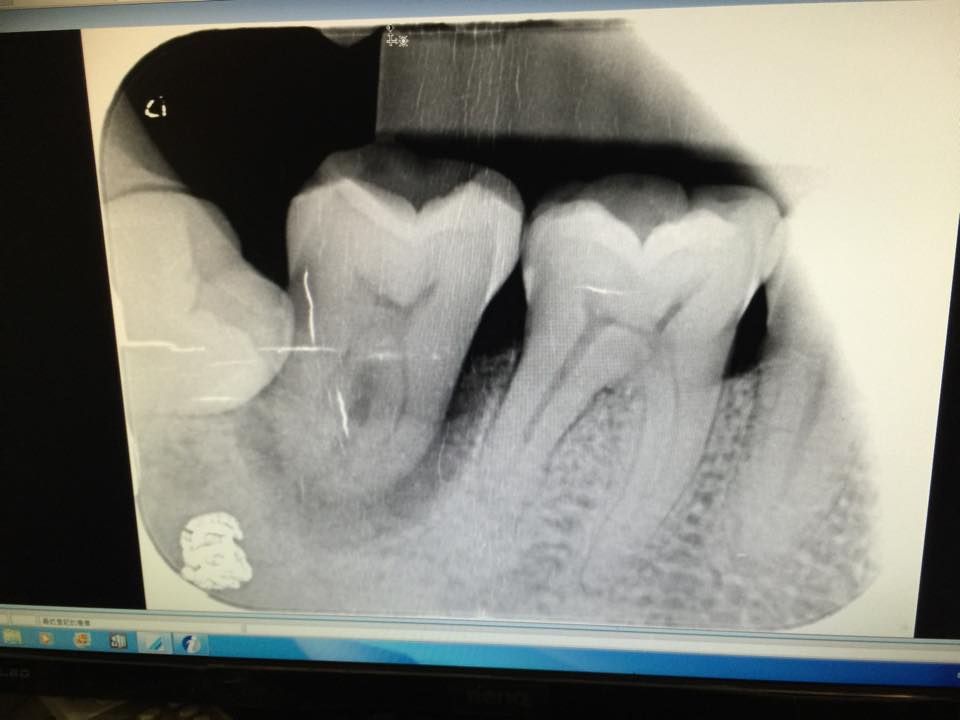

二十幾年來,好像都沒事,但近幾年終於看到後果。智齒的確壓迫臼齒,讓它下面發炎,但牙刷、牙間刷、牙線,都清理不到。

昨天去找牙醫拔掉這顆搖晃的臼齒,兩三下很輕鬆。但我的牙醫要幫我做「自體植牙」,也就是說,要把智齒拔出來,種在臼齒的洞裡。結果,智齒埋在牙骨裡,不想出來。折騰半天,最後只好把肉縫一縫,不去吵這顆沈睡四十幾年的智齒。我的牙醫是我見過最棒的牙醫,但我的智齒實在不想出來,又不能破壞它,所以就別煩它了。